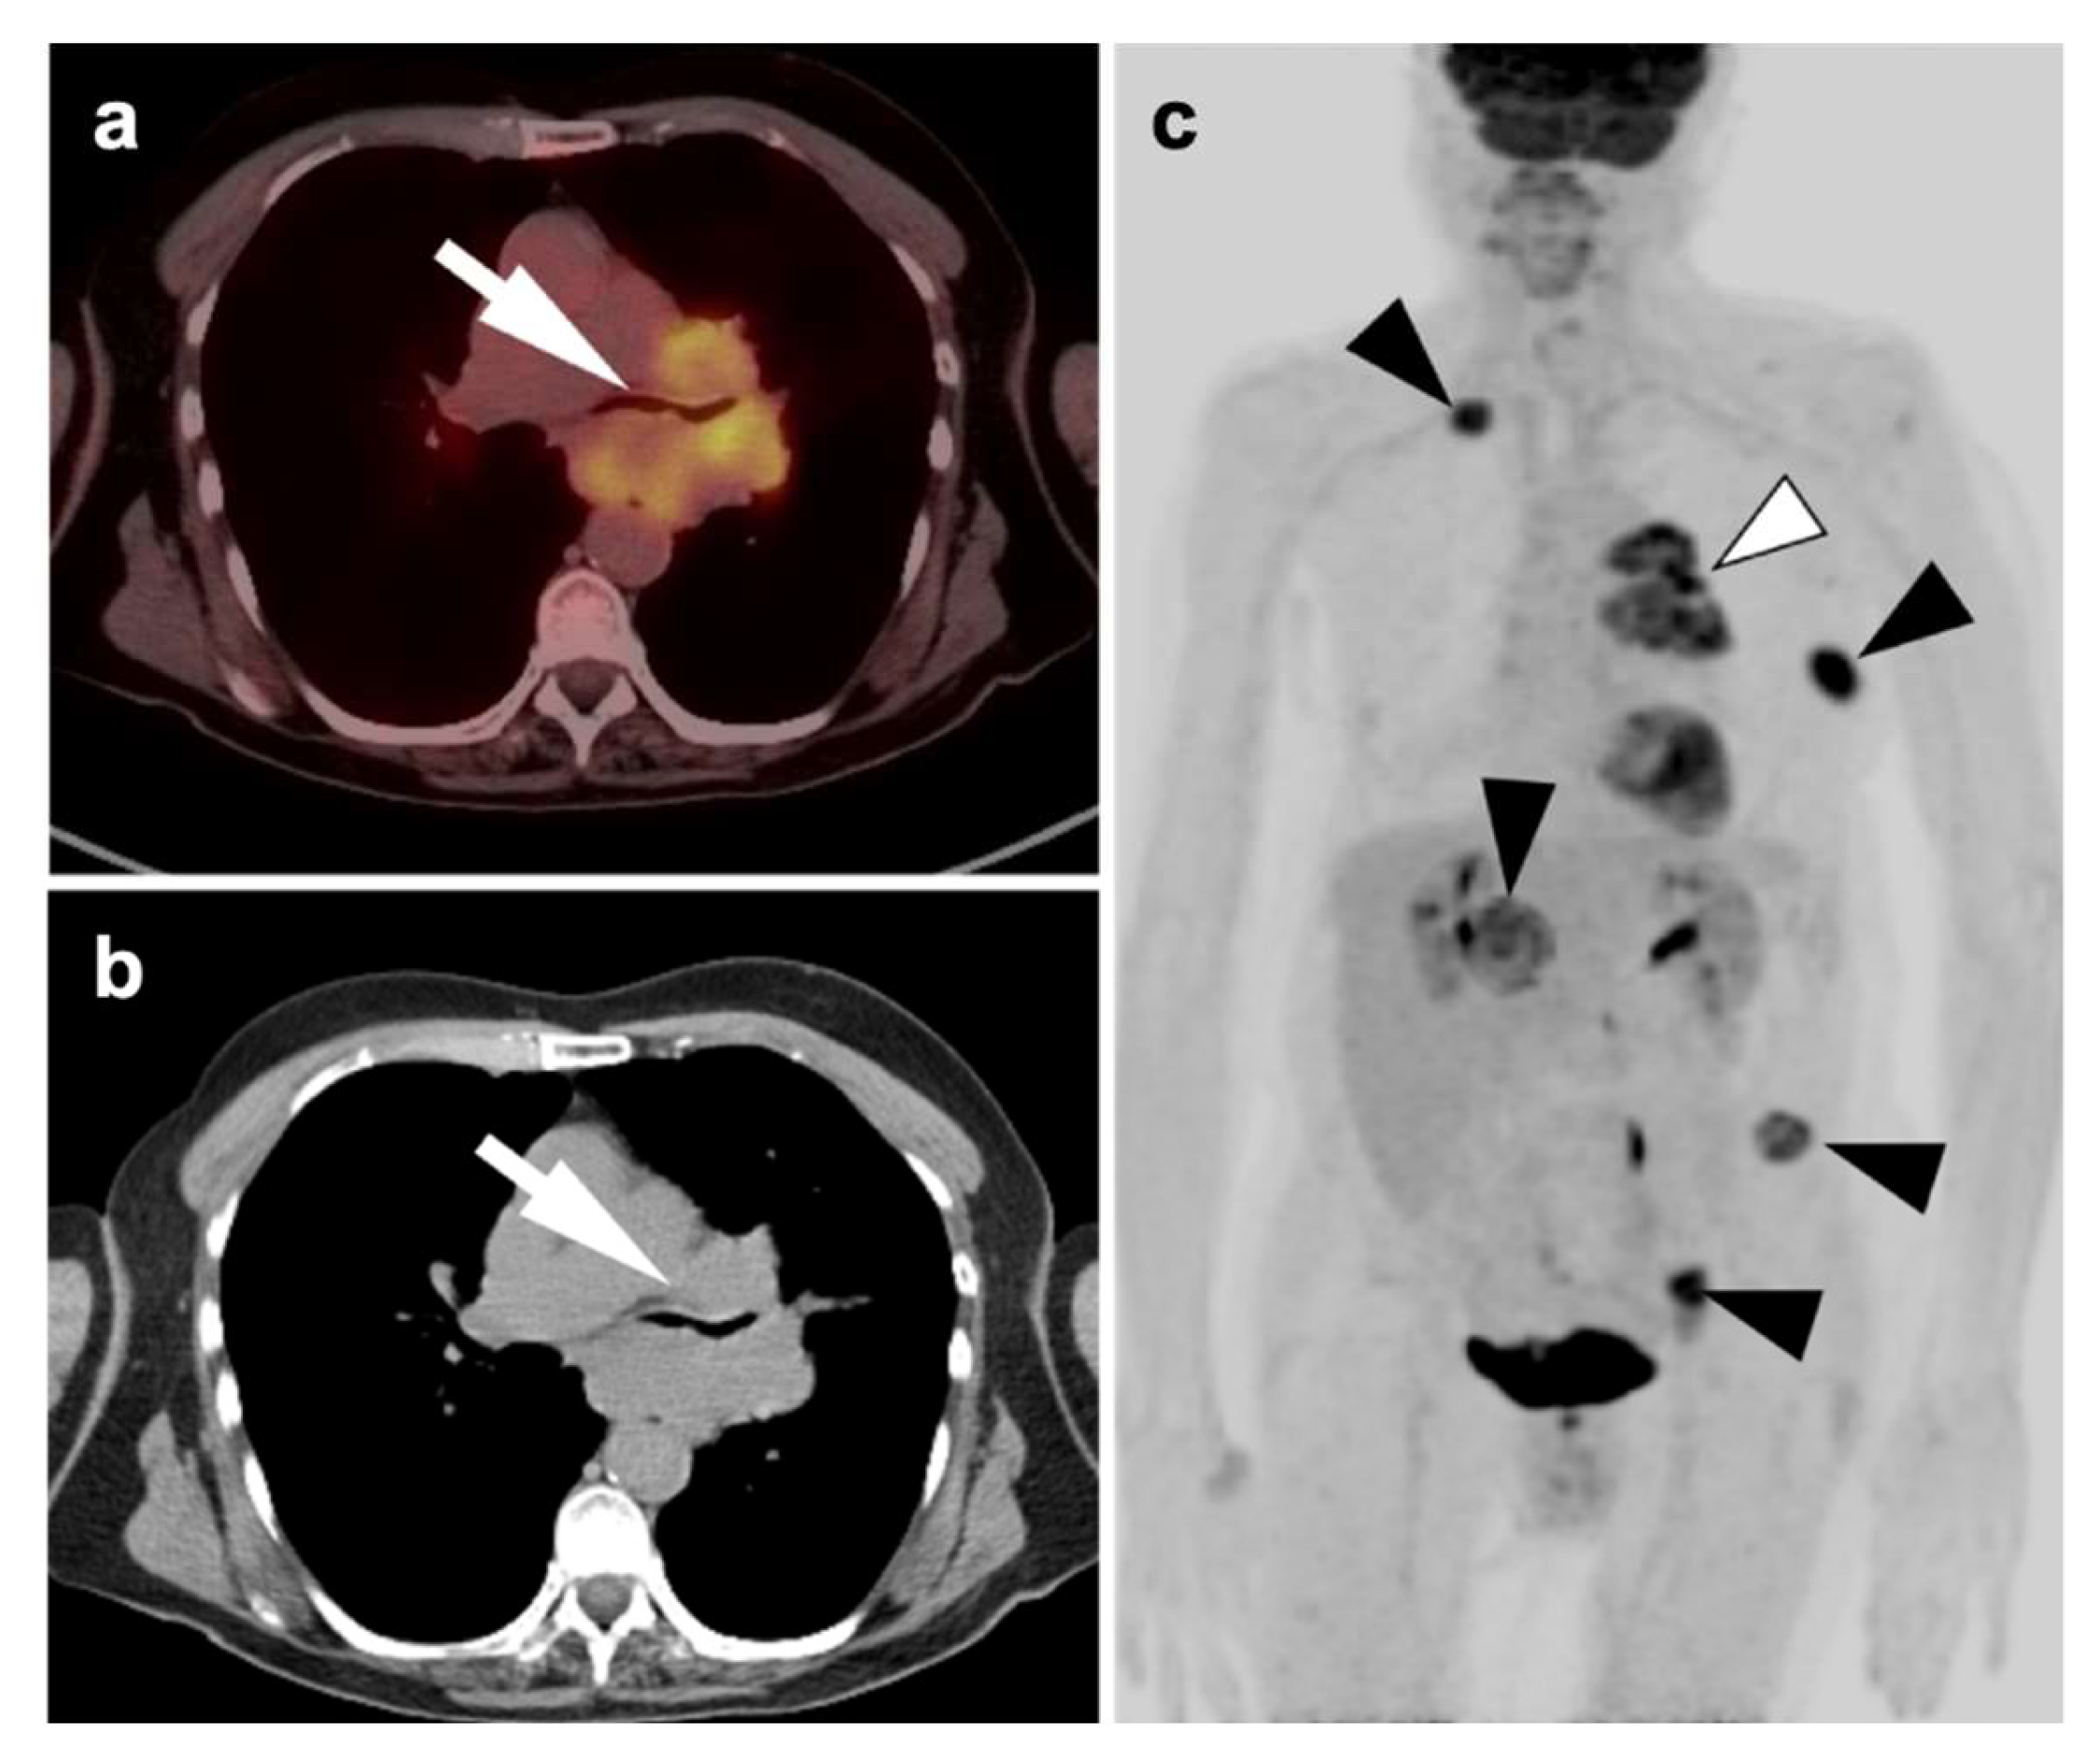

Nearly half of all patients with NSCLC have distant metastatic disease at initial diagnosis and identification of distant metastases is of major importance in the management and prognosis. Additionally, among patients who have been treated with radical and supposedly curative therapy, approximately 20% are likely to develop recurrent disease due to undetected foci of metastasis at initial M staging. Distant metastases are most commonly seen involving the brain, skeleton, liver, and adrenal glands in descending order of frequency (Figure 10) [31]. Traditional evaluation for distant metastatic disease includes CT scans of chest, abdomen, and pelvis, brain imaging with CT or MRI and bone scintigraphy [2]. However, FDG PET-CT has been shown to be great utility in M staging of the patients with NSCLC, specifically if the patients present with clinical manifestations of metastatic disease. Additionally, FDG PET-CT has been shown to provide more pertinent information during the preoperative assessment than is CT alone, except in the assessment of brain metastases, in a situation where the two modalities yield similar results [32]. For staging mediastinal lymph nodes, diffusion-weighted imaging MRI (DWI) and FDG PET-CT showed similar performance in staging of mediastinal lymph nodes, supporting the idea that DWI may offer an alternative to FDG PET-CT in some cases [33].

2.4. Small Cell Lung Cancer

Small cell lung cancer (SCLC) is an extremely aggressive tumor type which accounts for about 10–15% of all lung cancer cases [38,39]. It originates from neuroendocrine precursor cells and is characterized by rapid growth and early metastatic potential, with approximately 70% of patients presenting initially with metastases [40]. Up to 10–25% of patients with SCLC have brain metastases at the time of initial diagnosis and an additional 40–50% will develop brain metastases during the course of their disease. Although SCLC is usually chemo-sensitive in the early stages and sensitive to radiation therapy, most patients with SCLC will experience recurrent disease leading to death. Over 95% of patients with SCLC are either current or former smokers [2]. According to the Veterans Administration Lung Group’s criteria, SCLC has been traditionally divided into two stages—a binary system of staging—limited disease and extensive disease [41]. Limited-stage disease SCLC (LD-SCLC) is disease confined to ipsilateral hemithorax, mediastinum (including contralateral mediastinal nodes), and ipsilateral supraclavicular nodal involvement, which can be encompassed within a single radiation field (Figure 11) [42]. Extensive-stage disease SCLC (ED-SCLC) is spread beyond the ipsilateral hemithorax including hematogenous metastatic disease and presence of malignant pleural or pericardial effusion (Figure 12) [39,43]. Standard therapy for patients with LD-SCLC includes chemotherapy in conjunction with radiation therapy. Due to high potential for developing brain metastases in this group of patients, palliative cranial radiation is also indicated to increase overall survival. In ED-SCLC, only systemic chemotherapy is considered, as a palliative treatment, because long-term survival in these patients is rare [43,44]. According to the more recently adopted AJCC (American Joint Commission on Cancer) TNM staging system 8th edition, there is no significant difference between NSCLC and SCLC in the staging system [26]. The NCCN Panel adopted a combined approach for staging SCLC using both the AJCC TNM staging system and the VA scheme for SCLC. In applying the TNM classification to the VA system, the so-called limited-stage SCLC is defined as stage I–III (any T, any N, and M0, respectively), which can be effectively treated with definitive radiation therapy and extensive-stage SCLC is defined as stage IV (any T, any N and M1a/b) or T3–T4, harboring multiple lung nodules or tumor volume that is too large to be encompassed in a tolerable radiation plan/field.